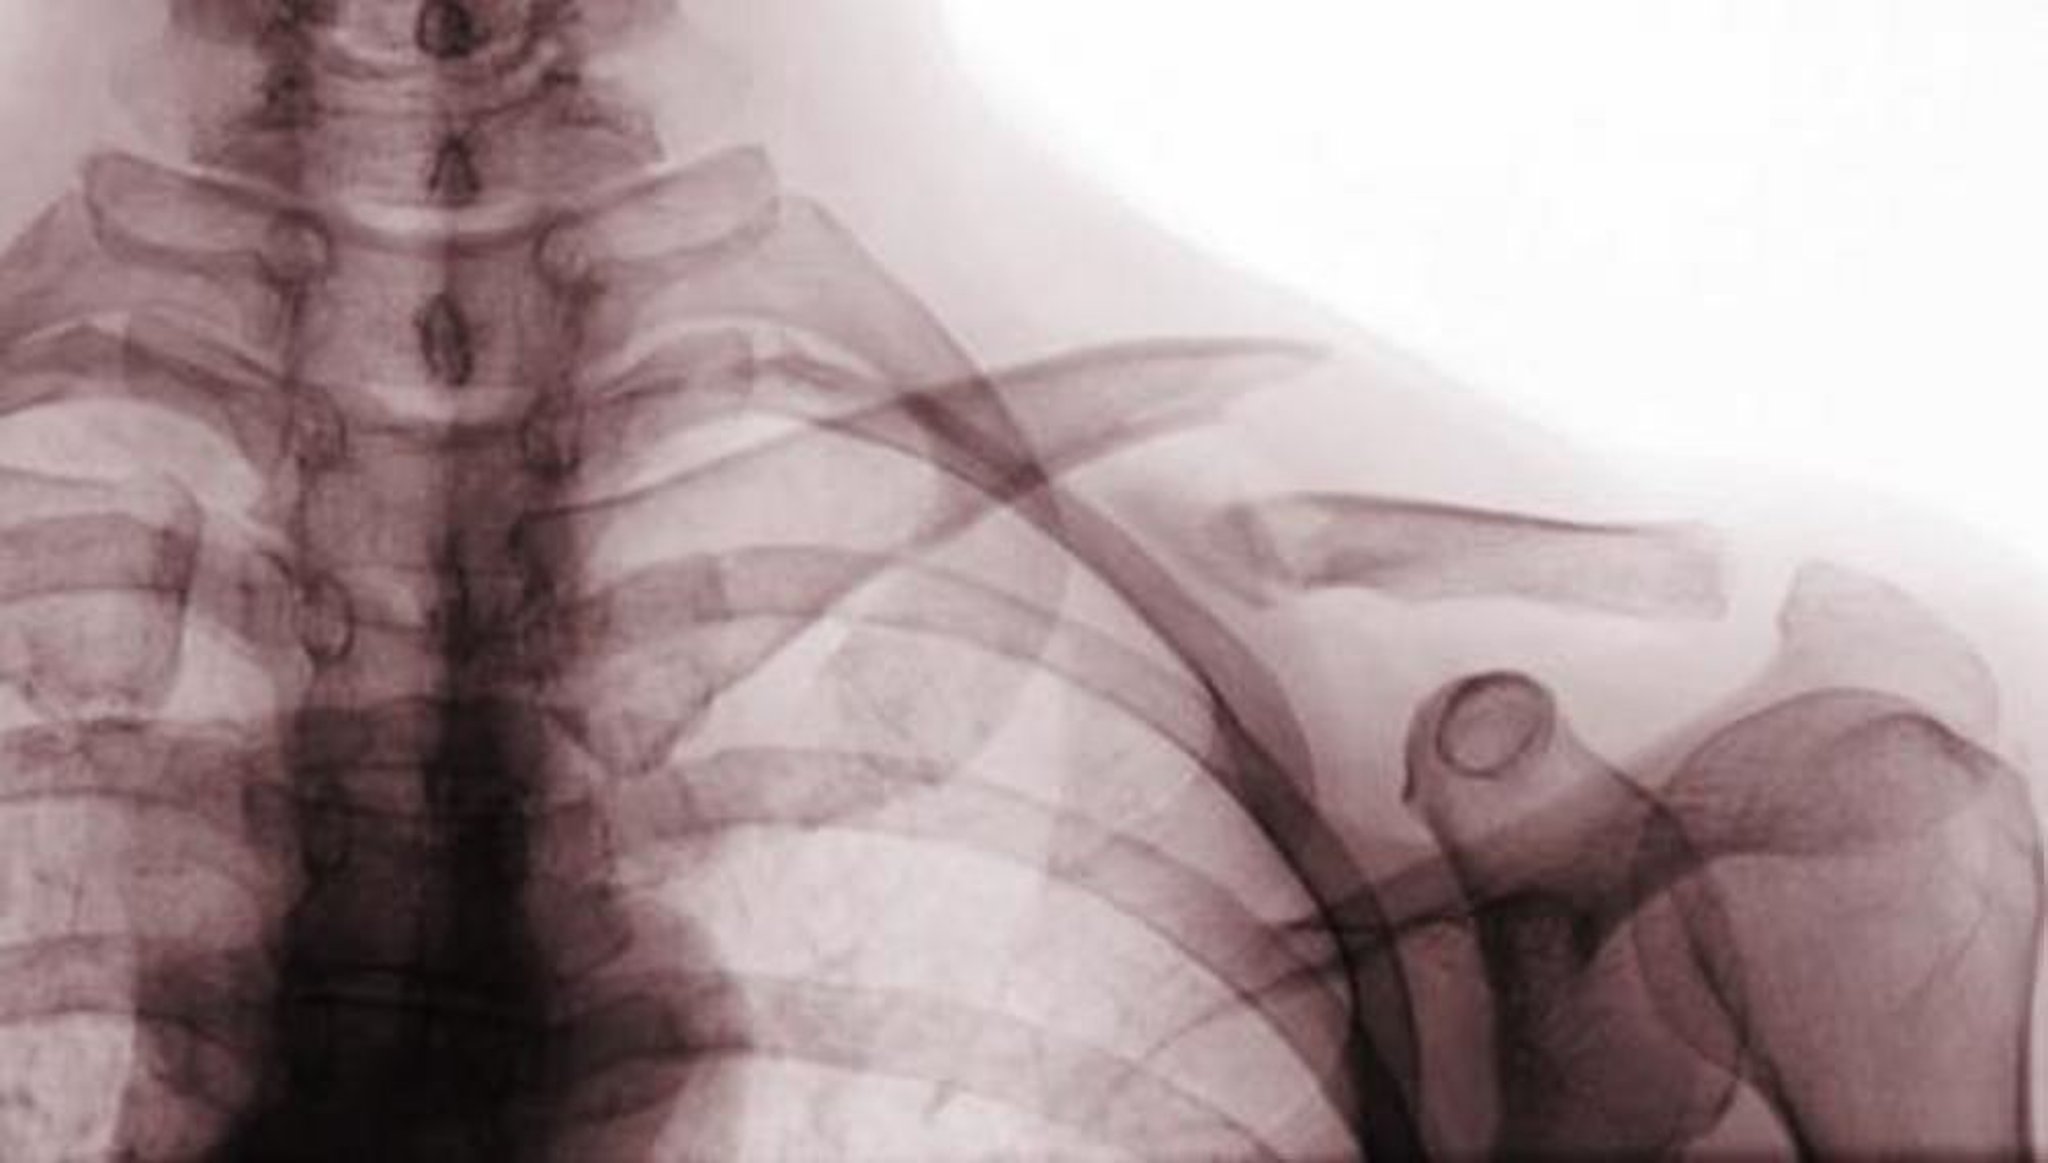

Essa radiografia ântero-posterior mostra uma fratura deslocada do terço médio da clavícula (fratura classe A).

Scott Camazine/SCIENCE PHOTO LIBRARY